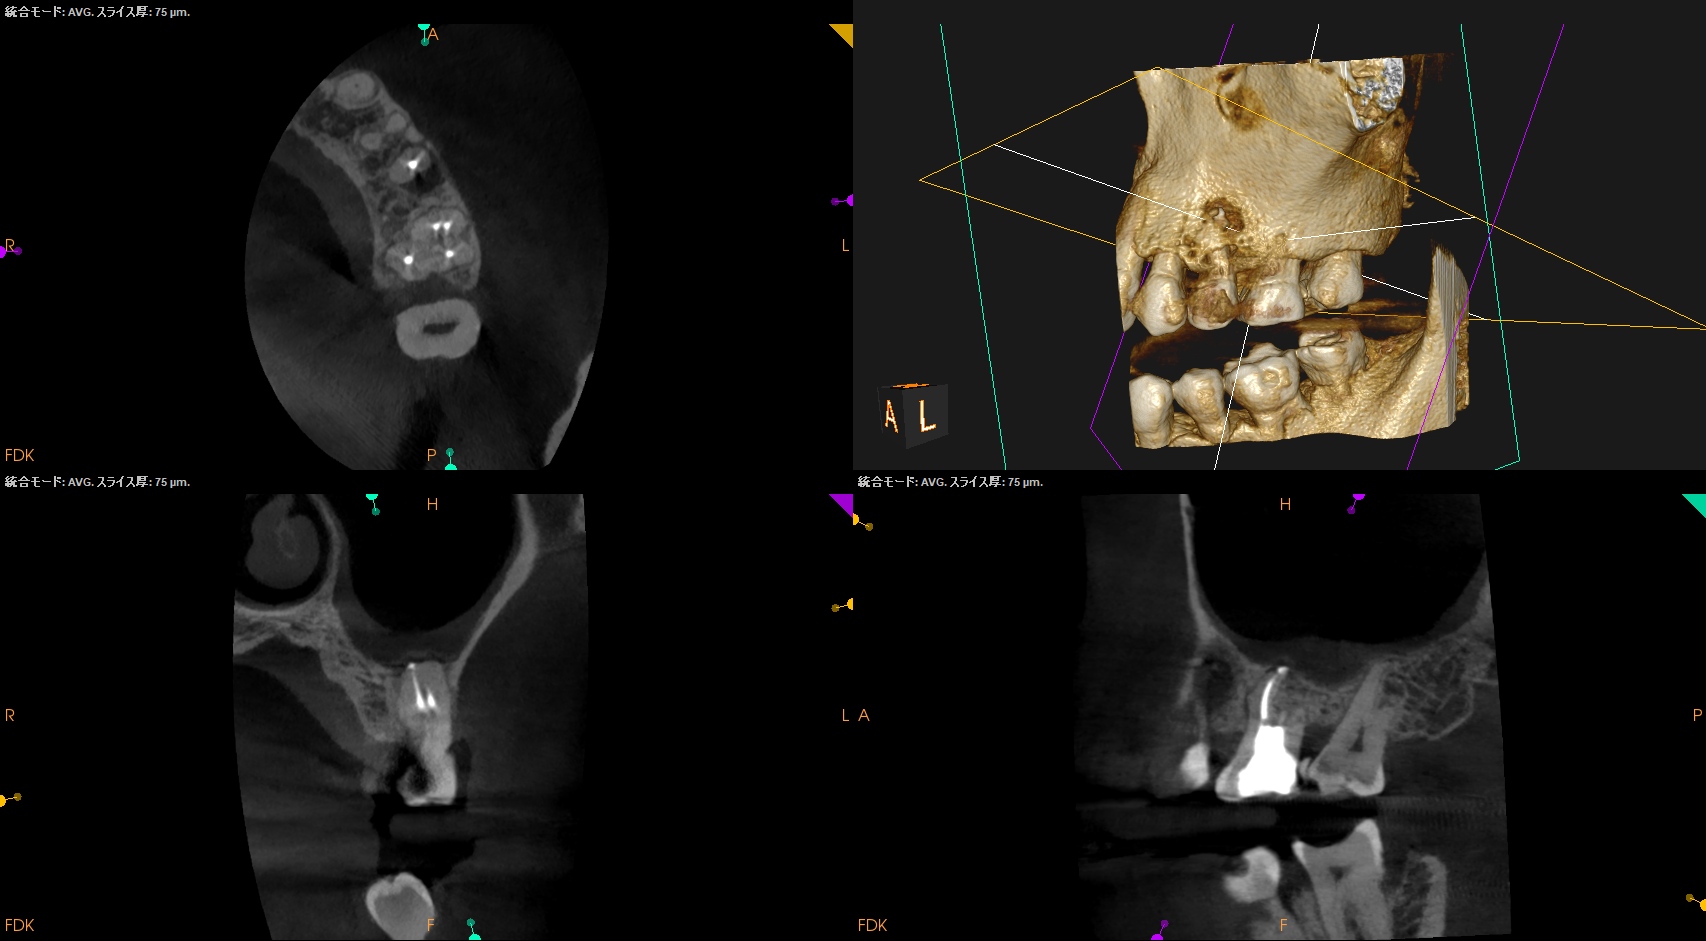

CBCTも撮影した。

これはマストの医療行為である、と私からは告げておこう。

さておき、#13にも病変があるのがわかるので#13も分析した。

#13

#13は#14よりも大きな根尖病変がある。

ここも治療が必要だろう。

Pulp Dx: Previously initiated therapy

Periapical Dx: Symptomatic apical periodontitis

Recomended Tx: Re-RCT

が、いずれにしてもこの治療での最大のポイントになるのはMB2がどこにあるか?である。

MB2の根尖部にはCBCTで根尖病変があるからだ。

さて皆さんは気が付いただろうか?

作業長が術前に予測したCBCTでの作業長に近似していること

を。

これが、

CBCTの威力

である。